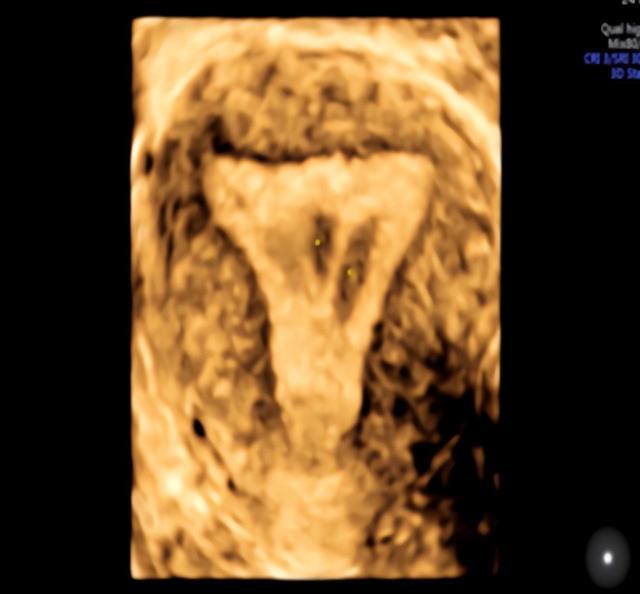

下图是正常宫腔,呈倒置三角形态。